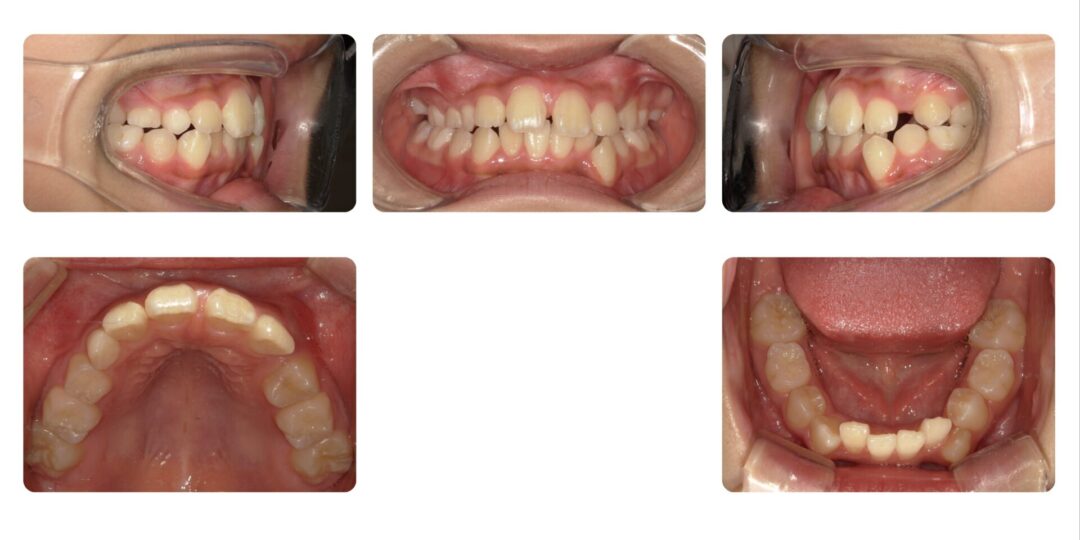

矯正治療前

初診時7歳

第一期治療 上顎拡大床(必要があれば下顎にも装置を増やす)

3年2ヶ月

自由診療 基本料金¥330,000 処置料¥3,300